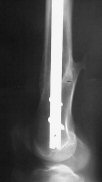

THX, initial images are

1,

2.

At that moment we had in stock only the 10 mm solid nails so of course there was no idea about early weight bearing. But it was quite enough for early knee ROM excersises (see attached). Two locking screws through the distal block provided that.

A new toy is more interesting and fashionable. And anyway it is not panacea, i have already seen presentations with LISS failures like the attached one presented by D.Seligson. And people also demonstrated incisions say that the method is not so LESS invasive as it supposed to be.